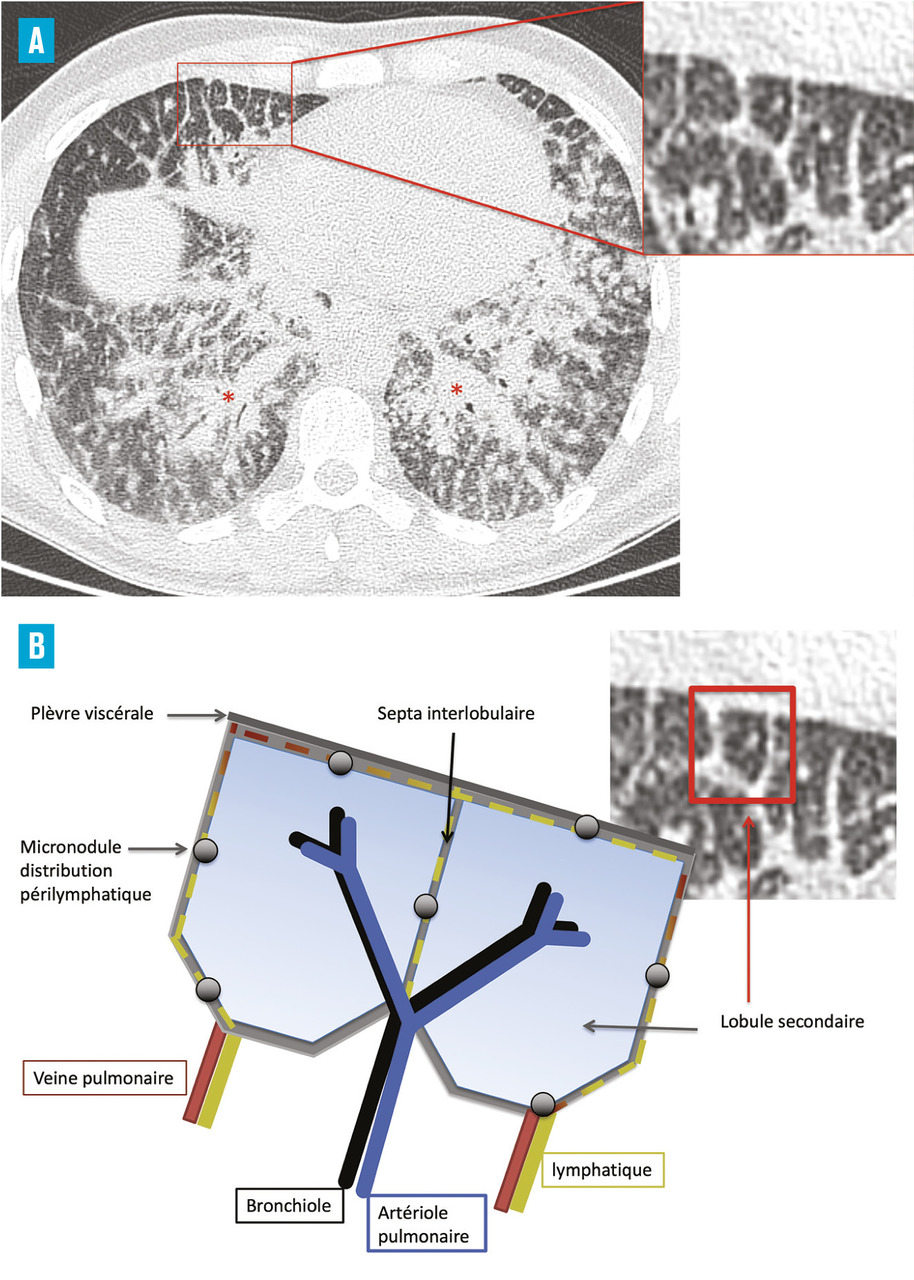

La tomodensitométrie thoracique a un grand intérêt diagnostique surtout en cas de présentation peu typique. Le tableau typique32 (fig. 2) est celui de l’association d’adénopathies médiastino-hilaires bilatérales et symétriques associées à des micronodules de distribution périlymphatique (les micronodules suivent les trajets lymphatiques et se retrouvent le long des axes péribronchovasculaires, à l’échelle du lobule secondaire dans les septums interlobulaires, en sous-pleural et notamment le long des scissures) prédominant dans les territoires supérieurs et moyens (fig. 3). Ce tableau permet de prédire avec plus de 95 % de sécurité un diagnostic de sarcoïdose chez 80 % des patients.2, 33, 34 Dans les rares cas où des lésions non habituelles prédominent, comme le verre dépoli ou les condensations, la présence d’adénopathies typiques ou de micronodules périlymphatiques même au second plan permet dans la plupart des cas de retenir le diagnostic de sarcoïdose.35, 36 La tomodensitométrie permet, en outre, de renseigner avec plus de précision sur le caractère réversible inflammatoire (micronodules, nodules) ou irréversible des lésions (fibrose). Les lésions de fibrose pulmonaire prédominent dans les territoires supérieurs moyens et périhilaires. Le tableau le plus typique est celui de réticulations avec distorsion péribronchovasculaire prédominant dans les lobes supérieurs dont le volume est réduit. Des adéno- athies calcifiées bilatérales peuvent témoigner de la déclaration ancienne de la maladie.37